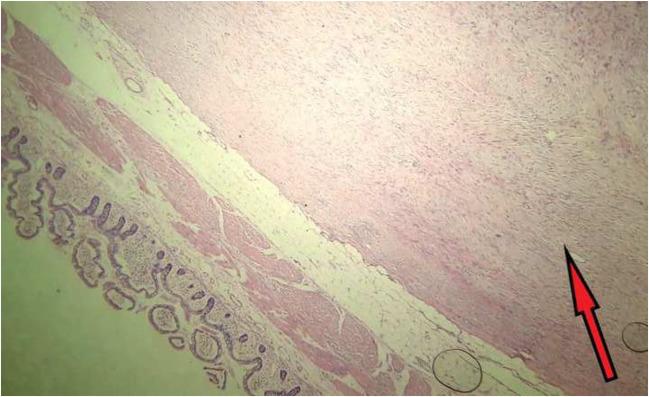

Mesenteric fibromatosis-desmoid tumor of mesentery is a rare benign soft tissue tumor of mesentery. On CT, it mimics gastrointestinal stromal tumor (GIST).

A 44-year-old female with small intestinal mass, preoperatively diagnosed radiologically and pathologically as GIST.

Mesenteric fibromatosis is a rare tumor often mistaken for GIST. Histopathology and immunohistochemistry is the key as management of both the tumors differs.

肠系膜纤维瘤病——肠系膜硬纤维瘤是一种罕见的肠系膜良性软组织肿瘤。在CT上,它类似胃肠道间质瘤(GIST)。

一名44岁女性,有小肠肿物,术前经影像学和病理诊断为GIST。

肠系膜纤维瘤病是一种罕见肿瘤,常被误诊为GIST。组织病理学和免疫组化是关键,因为这两种肿瘤的治疗方法不同。